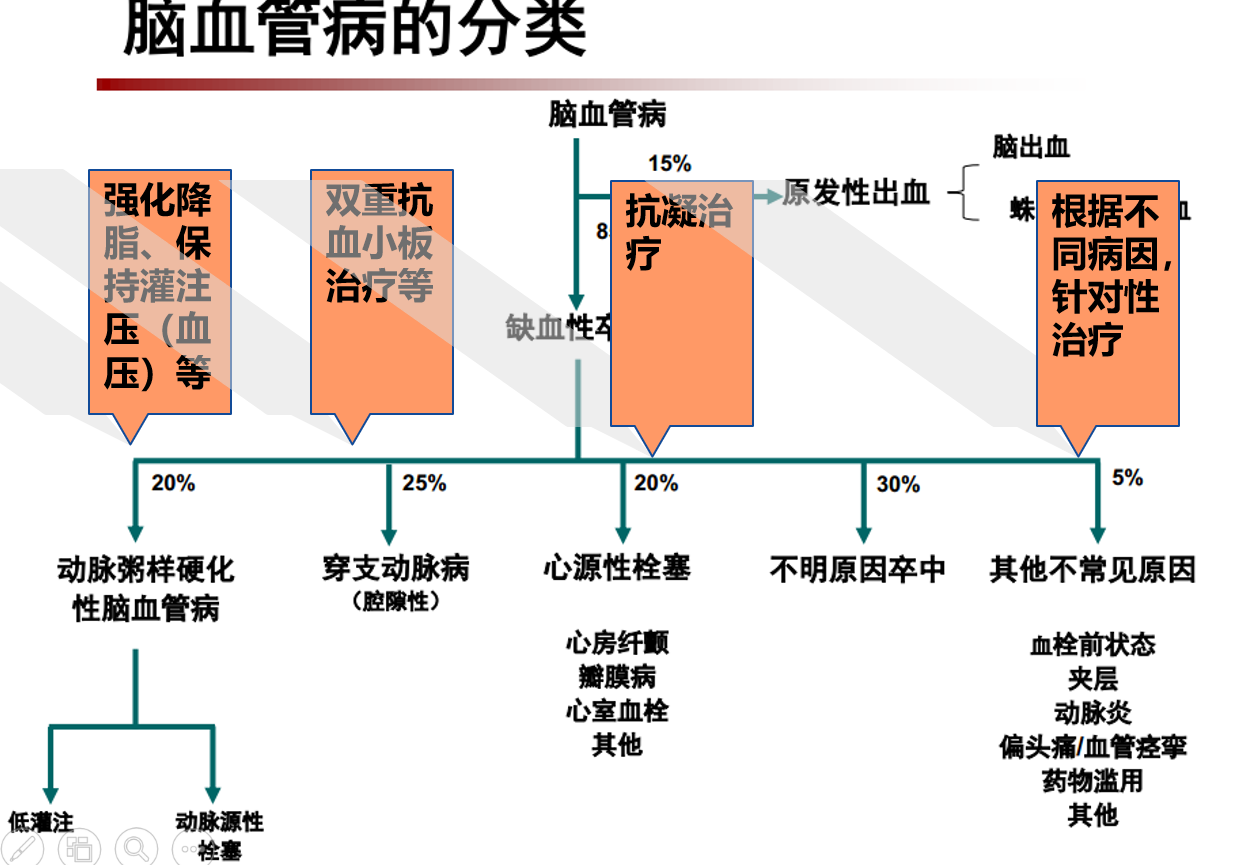

①脑梗死病因分类

②根据不同的病因,使用不同的预防方案

根据病因分型,卒中医生通常会为患者制订个体化的二级预防方案,减低中风再发的风险。